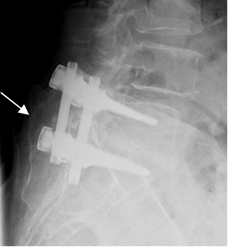

El estudio inicial con Rx simple es de mucha utilidad, por el amplio campo de visión que da. Las protecciones dinámicas permiten valorar la integridad de la fusión y el grado de movilidad. (28). (Fig 131 y 132).

Fig 132. Puente oseo.

A: Rx lateral. Formación de puente oseo, por detrás del material de osteosíntesis.